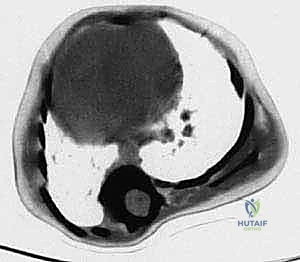

- التصوير بالرنين المغناطيسي (MRI): فحص إلزامي ومفصلي في حالات جنف الأطفال المبكر. يطلبه الدكتور هطيف للتأكد من عدم وجود تشوهات داخل الحبل الشوكي (مثل الأورام، أو تكهف النخاع) التي قد تسبب الجنف.

- التصوير المقطعي المحوسب (CT Scan) ثلاثي الأبعاد: يوفر رؤية دقيقة للتشريح العظمي المعقد، وهو ضروري جداً للتخطيط الجراحي قبل زراعة قضبان النمو لتحديد أماكن وضع المسامير بدقة متناهية.